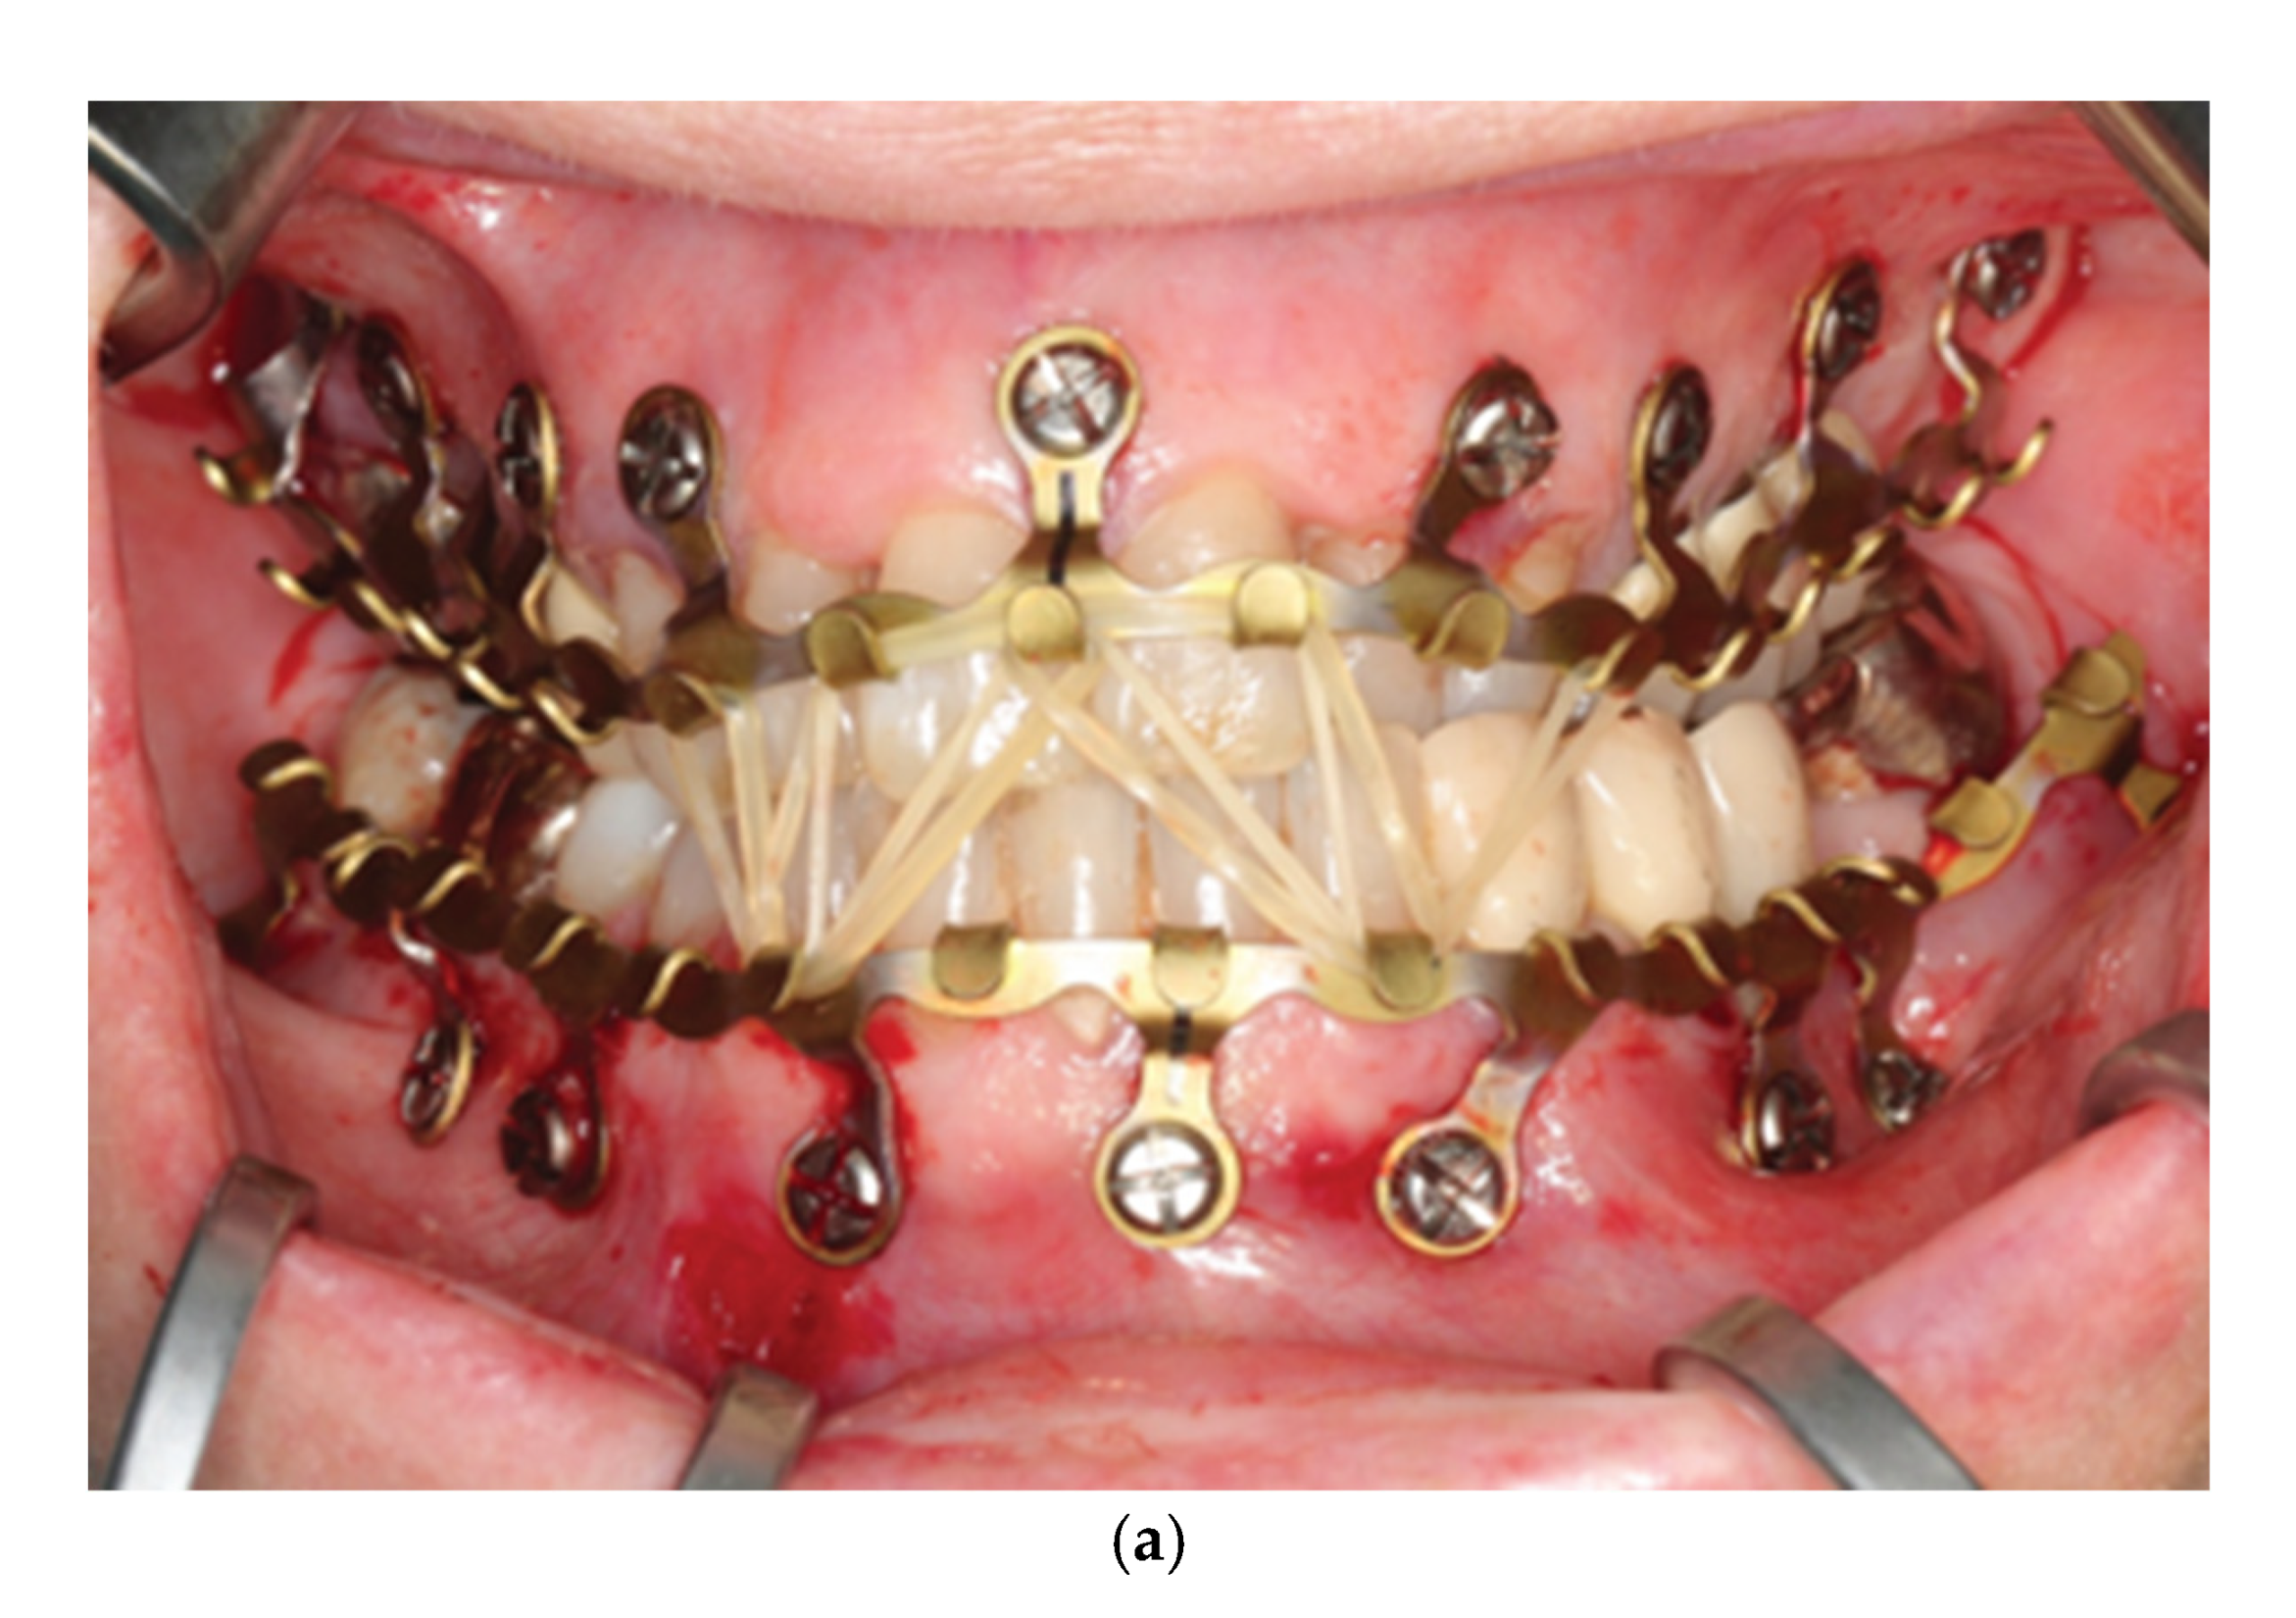

3.2. Self-Made Hybrid Erich Arch Bars – Modifications

3.3. Hybrid Arch Bars – Self-Made EAB Modifications - Clinical Studies in Comparison to Former MMF Modalities